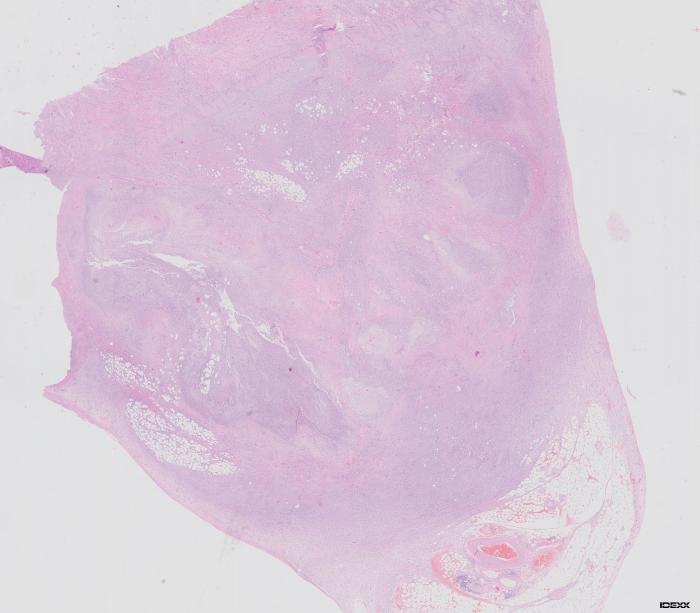

Histopatológicamente, la zona de engrosamiento intestinal se caracterizó por un intenso infiltrado de neutrófilos, macrófagos y, en menor medida, linfocitos y células plasmáticas, que afectaba predominantemente a la mucosa y se extendía al tejido muscular y mesenterio adyacente. Este proceso inflamatorio se acompañaba de hemorragia abundante y leve reacción de fibroplasia. Multifocalmente, se observaron pequeños agregados de macrófagos espumosos y ocasionales células gigantes multinucleadas dispuestos alrededor de espacios de contenido eosinofílico anfofílico pálido, correspondientes a vasos linfáticos dilatados bordeados por una fibroplasia concéntrica leve. Lesiones similares se identificaron también en la submucosa de las zonas marginales, no pudiéndose descartar, por lo tanto, la afectación de otros segmentos intestinales. La mucosa restante mostró hiperplasia moderada del tejido linfoide asociado a mucosa y un infiltrado inflamatorio mixto, compuesto por un número moderado de neutrófilos, linfocitos y células plasmáticas. Estos hallazgos fueron consistentes con linfangitis lipogranulomatosa focal grave (Figura 3A-D).

Figura 3A-D. Histopatología intestinal que evidencia linfangitis lipogranulomatosa focal grave, con infiltrado inflamatorio mixto, hemorragia, fibroplasia leve y dilatación de vasos linfáticos con macrófagos espumosos y células gigantes multinucleadas.